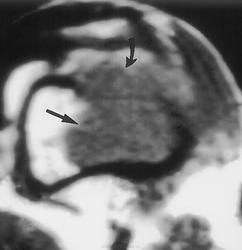

Гигантоклеточная опухоль.

Злокачественная гигантоклеточная  опухоль возникает из доброкачественной (частота 10-20%). После операции возможно появление рецидива опухоли.